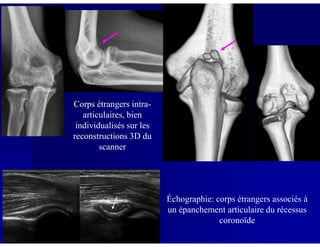

Corps étrangers intra-

articulaires, bien

individualisés sur lesindividualisés sur les

reconstructions 3D du

scanner

Échographie: corps étrangers associés à

un épanchement articulaire du récessus

coronoïde

TDM en coupe axiale, avec reconstructions coronale et sagittale:

ostéochondrite associée à des corps étrangers intra-articulaires

TDM: bilan pré-opératoire:

défect (niche) ostéochondral

+ corps étrangers en regard

de la fossette coronoïde et dude la fossette coronoïde et du

récessus radio-ulnaire

proximal